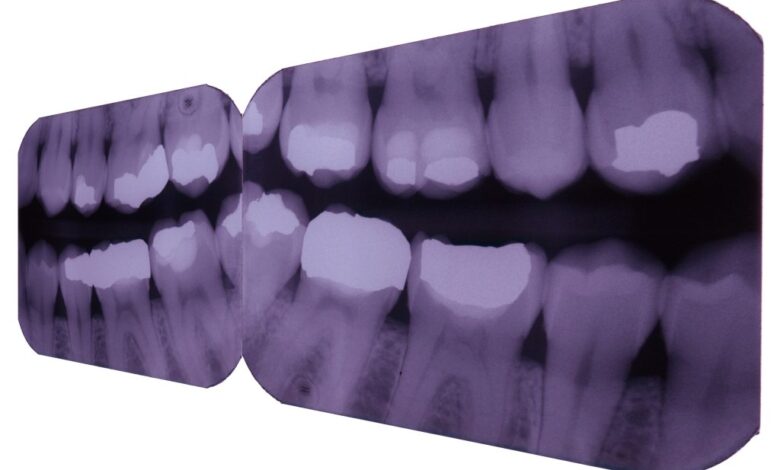

Рентгеновские снимки зубов и челюсти могут быть назначены по различным причинам. Они позволяют специалистам:

- Оценить состояние зубов и корней;

- Выявить кариес, воспаления или кисты;

- Проверить костную ткань челюсти;

- Подготовиться к проведению хирургических вмешательств;

- Контролировать эффективность лечения.